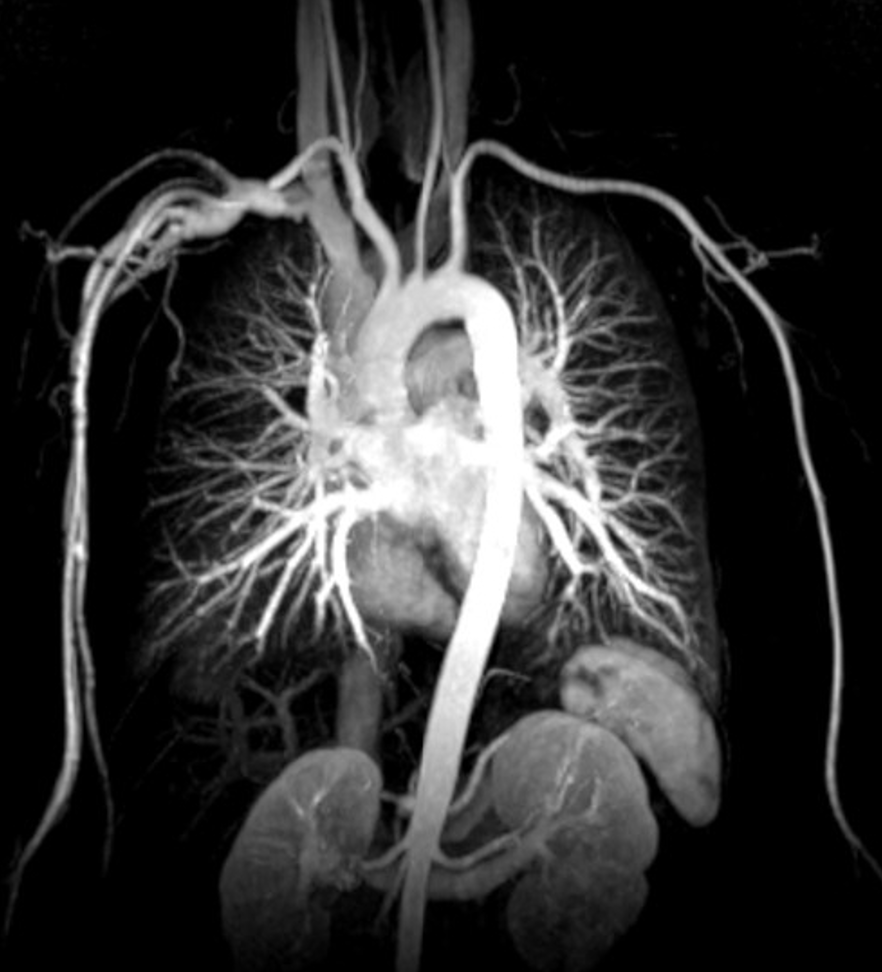

14. Coarctation of the aorta (narrowing or occlusion) in the region of ligamentum arteriosum limits delivery of blood to the descending aorta. (True)

15. Coarctation of the aorta changes the normal pattern of collateral circulation so that the posterior intercostal arteries supply retrograde blood flow to the descending aorta. (true)